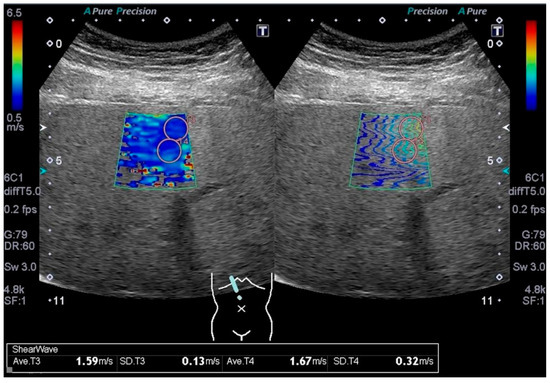

2.2. Data Collection and Measurement of Liver Stiffness